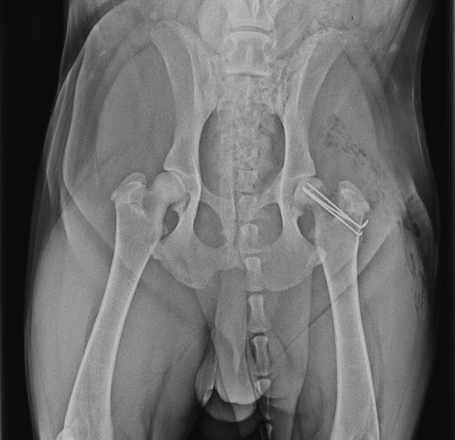

OFA (left) and PennHIP (right) radiographs on the same canine patient. The hips look reasonable on the OFA images (left) but the extreme laxity is readily evident on the PennHIP radiographs.

Dog with bilateral, staged double pelvic osteotomy (pre-operative and 8 weeks post)